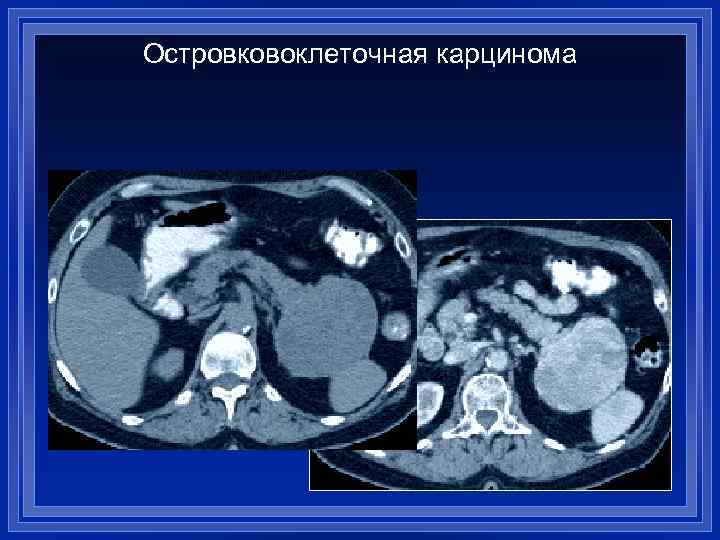

Островковоклеточная карцинома